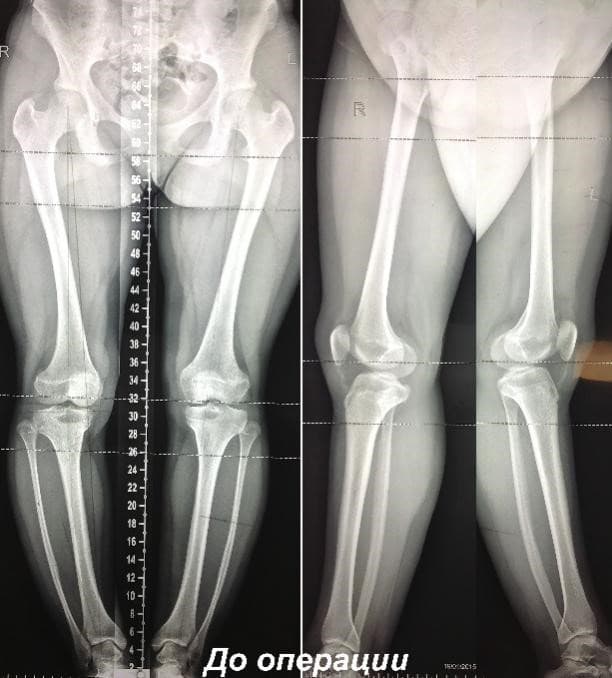

Примеры применения чрескостного остеосинтеза